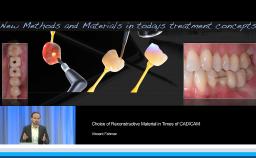

Part one of a two-part presentation gives a comprehensive overview of how to treat complex cases using an interdisciplinary approach in implant dentistry. From the prosthodontist’s point of view, the workflow starts with careful prosthetic planning by the use of wax-ups or set-ups, and in some cases orthodontic pretreatment is indicated. This lecture demonstrates how the prosthetic planning is then transferred by surgical templates to facilitate the correct 3D prosthodontically driven implant placement. In this workflow, the provisional prosthesis conditions the soft tissue in order to optimize esthetics prior to finalizing the prosthetic rehabilitation. This lecture includes a series of ‘Prosthetic Rules’ to serve as benchmarks for effective prosthodontically driven treatment.

- describe the workflow of careful prosthetic planning, surgical templates during implant placement, provisional prosthesis with soft tissue conditioning, and final rehabilitation